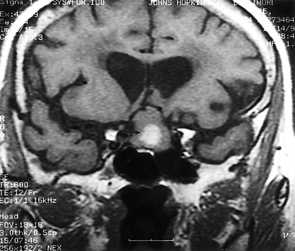

Кровоизлияние в мозжечок является следствием гипертонии и составляет около 10% всех случаев кровоизлияний в мозг. Обширное кровоизлияние может вызвать обструкцию 4 желудочка и гидроцефалию. Ранняя диагностика обычно осуществляется с помощью КТ. При МРТ головного мозга уже на вторые - третьи сутки кровь становится гипоинтенсивной на Т2-зависимых МРТ за счет превращения оксигемоглобина в дезоксигемоглобин. Эритроциты остаются неразрушенными. Дезоксигемоглобин на Т1-зависимых МРТ изоинтенсивен белому веществу. Процесс изменения гемоглобина идет снаружи внутрь, поэтому внутримозговое кровоизлияние имеет кольцевую структуру. На Т2-зависимых МРТ снаружи идет широкая зона гиперинтенсивного отека, в центре - резко гипоинтенсивное кольцо внутриэритроцитарного дезоксигемоглобина. Уже на 5-6 сутки дезоксигемоглобин превращается в метгемоглобин, который гиперинтенсивен на МРТ обоих типов зависимости.

КТ головного мозга. Кровоизлияние в мозжечок.

МРТ головного мозга. Аксиальная Т2-взвешенная МРТ. Кровоизлияние в мозжечок.